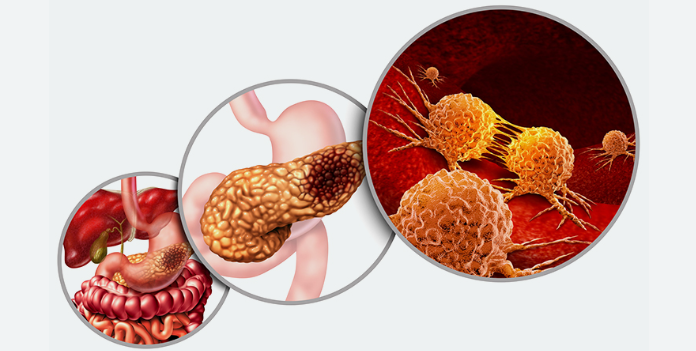

पैन्क्रियाटिक कैंसर

सबसे खतरनाक कैंसर पैन्क्रियाटिक कैंसर होता है। जिसे अग्राशय का कैंसर भी कहते है। पैन्क्रियाटिक कैंसर इसलिए सबसे खतरनाक माना जाता है क्योंकि इस कैंसर में शुरुआती लक्षण सामने नहीं आ पाते। पैन्क्रियाटिक कैंसर में मरीज के पेट दर्द, अपच या हल्की थकान होना, जिन्हें हम आम समस्या समझ बैठते है।

पैन्क्रियाटिक कैंसर का बहुत देर से चल पाता है। इस कैंसर का पता जब तक चल पाता है। तब तक ये स्टेज 3 या 4 मे पहुंच चुका होता है। पैन्क्रियाटिक कैंसर बड़ी तेजी से शरीर के दूसरे हिस्सों में फैलता है, खासकर लिवर, फेपड़े और पेट के आसपास बाकी कैंसर की तुलना में पैन्क्रियाटिक कैंसर के सर्वाइकल रेट केवल 5 साल है, जो करीब 10 % से भी कम है।

क्या है पैन्क्रियाटिक कैंसर के लक्षण

1- पेट के ऊपरी हिस्से में लगातार दर्द रहना

2- अचानक से वजन कम होना और भूख कम लगना

3-स्किन और आंखे पीली होना (पीलिया)

4-थकावट महसूस होना, हल्का बुखार रहना

5- भूख लगने के बावजूद खाना खाने का मन न होना

6-डार्क यूरीन और लाइट कलर स्टूल

7 – ऐसा कमर दर्द जो पेट तक आता हो